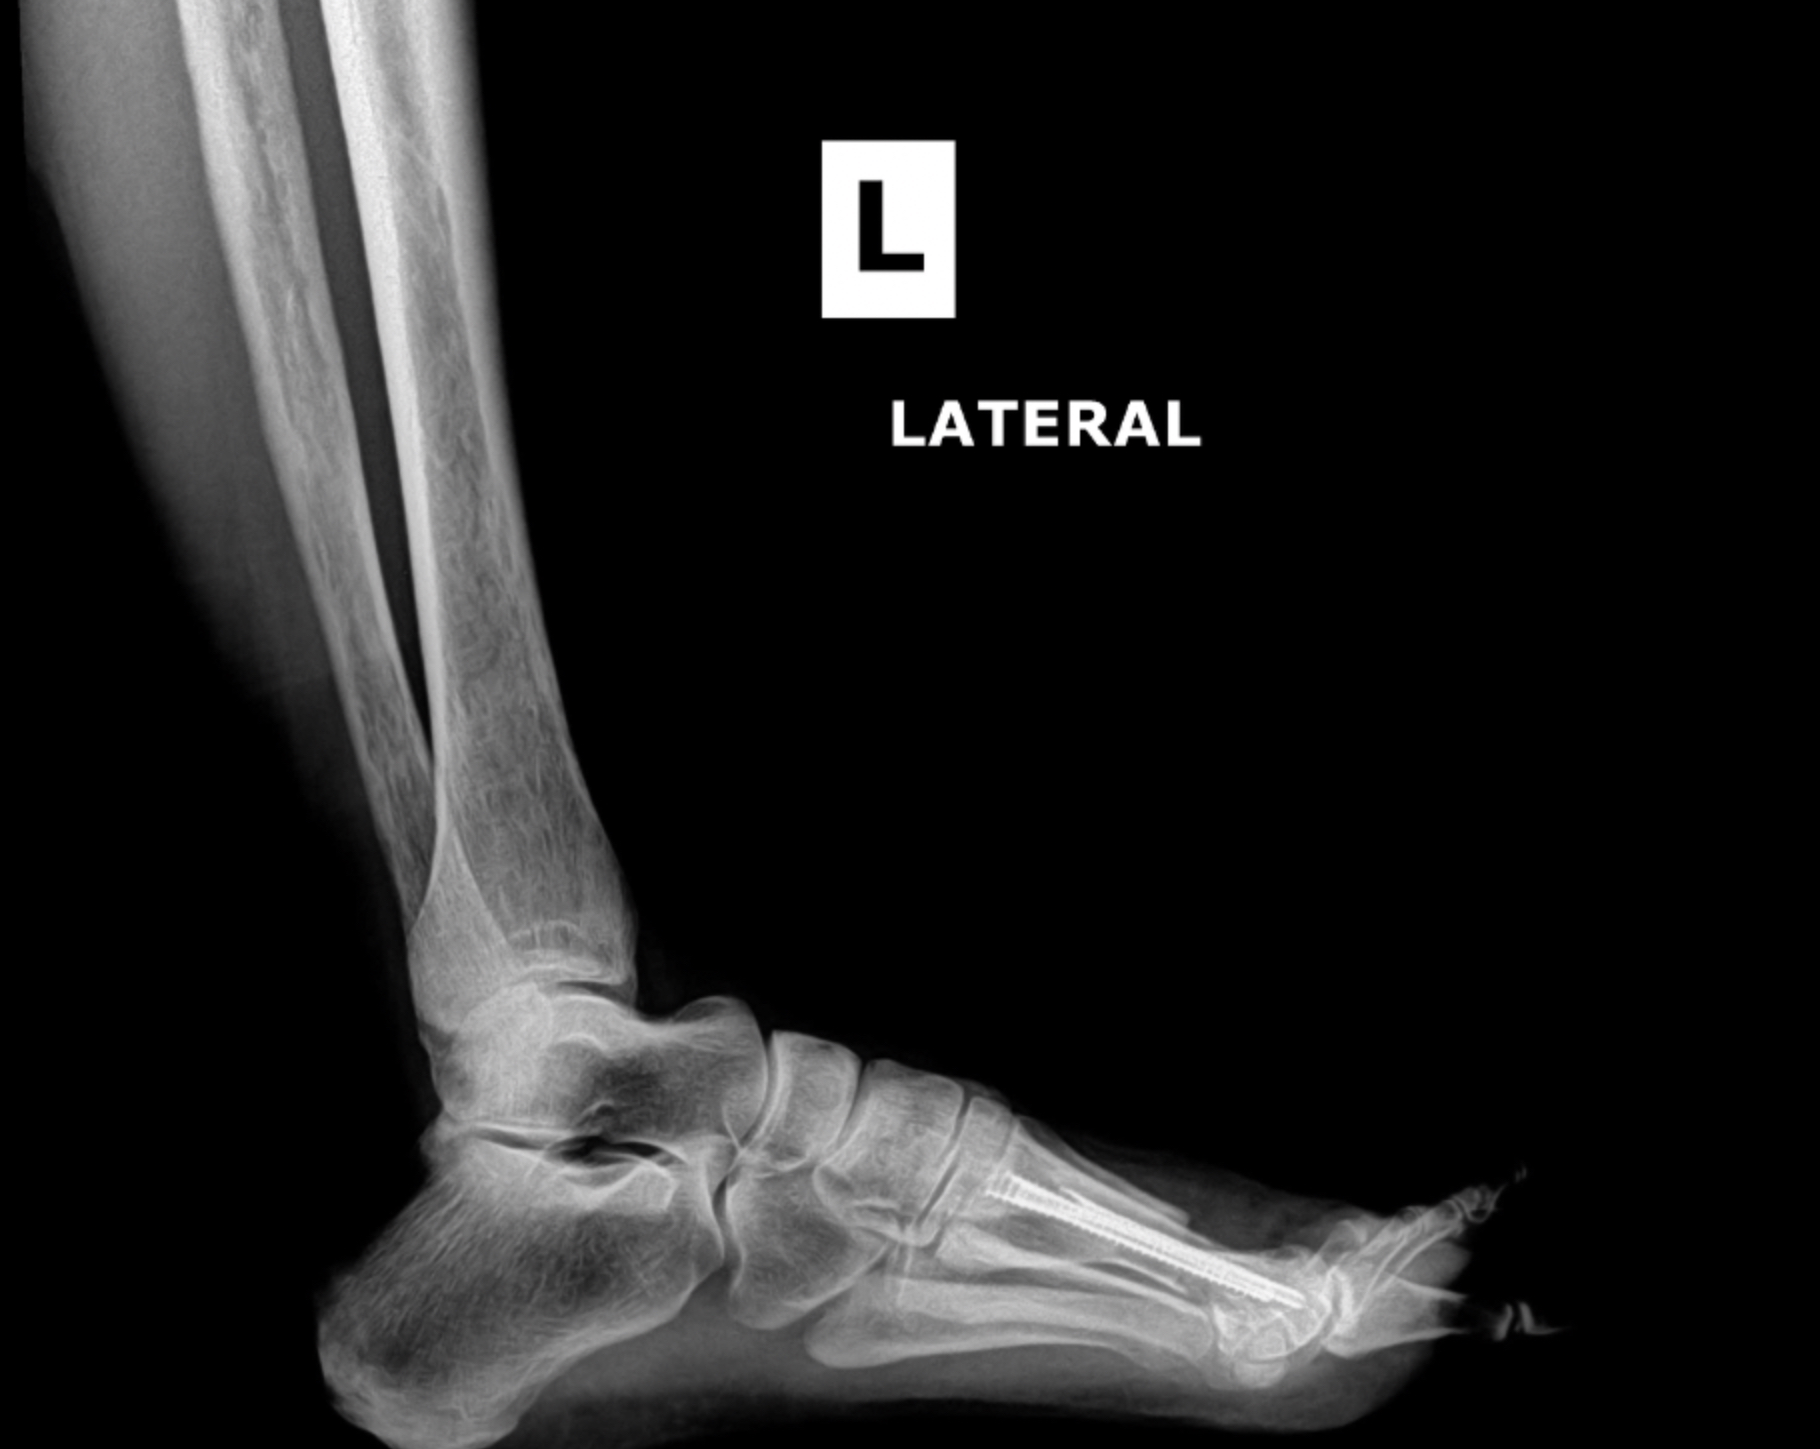

Total Ankle Replacement

Patient 1

Patient 2